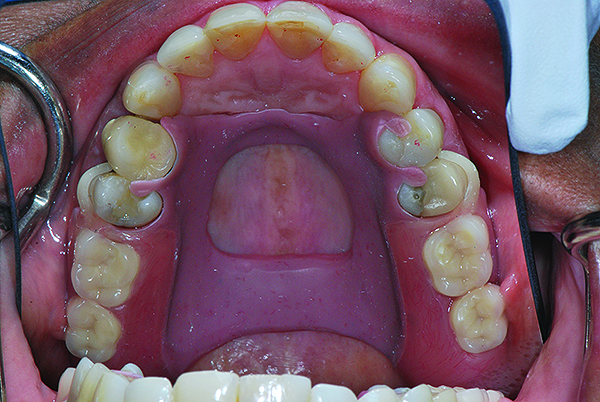

A 63-year-old African-American female presented at the University of North Carolina General Dentistry Student Clinic with a chief complaint that she was missing posterior teeth on both arches and said she would like to replace them (Figure 8).

The patient was concerned about esthetics because she was a school teacher. Her dental history revealed that she had removable partial cobalt chromium dentures that no longer fit and she had not used them for a long period. Her medical history at the initial examination revealed that she had type 2 diabetes mellitus, hypertension, and hyperlipidemia, all of which was controlled. However, she had no medical contraindication for dental care or oral surgical procedures.

Fig 8. Intraoral pre-operative photograph showing multiple missing posterior teeth in both arches.

Figure 8